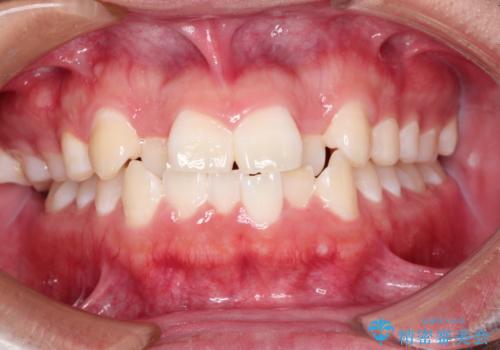

[インビザライン ライト] 短期間(3.5ヶ月)で終わるマウスピース矯正

![[インビザライン ライト] 短期間(3.5ヶ月)で終わるマウスピース矯正の症例 治療前](https://seimitsushinbi.jp/wp/wp-content/uploads/2020/02/C3-500x350.jpg?v=1580813654)